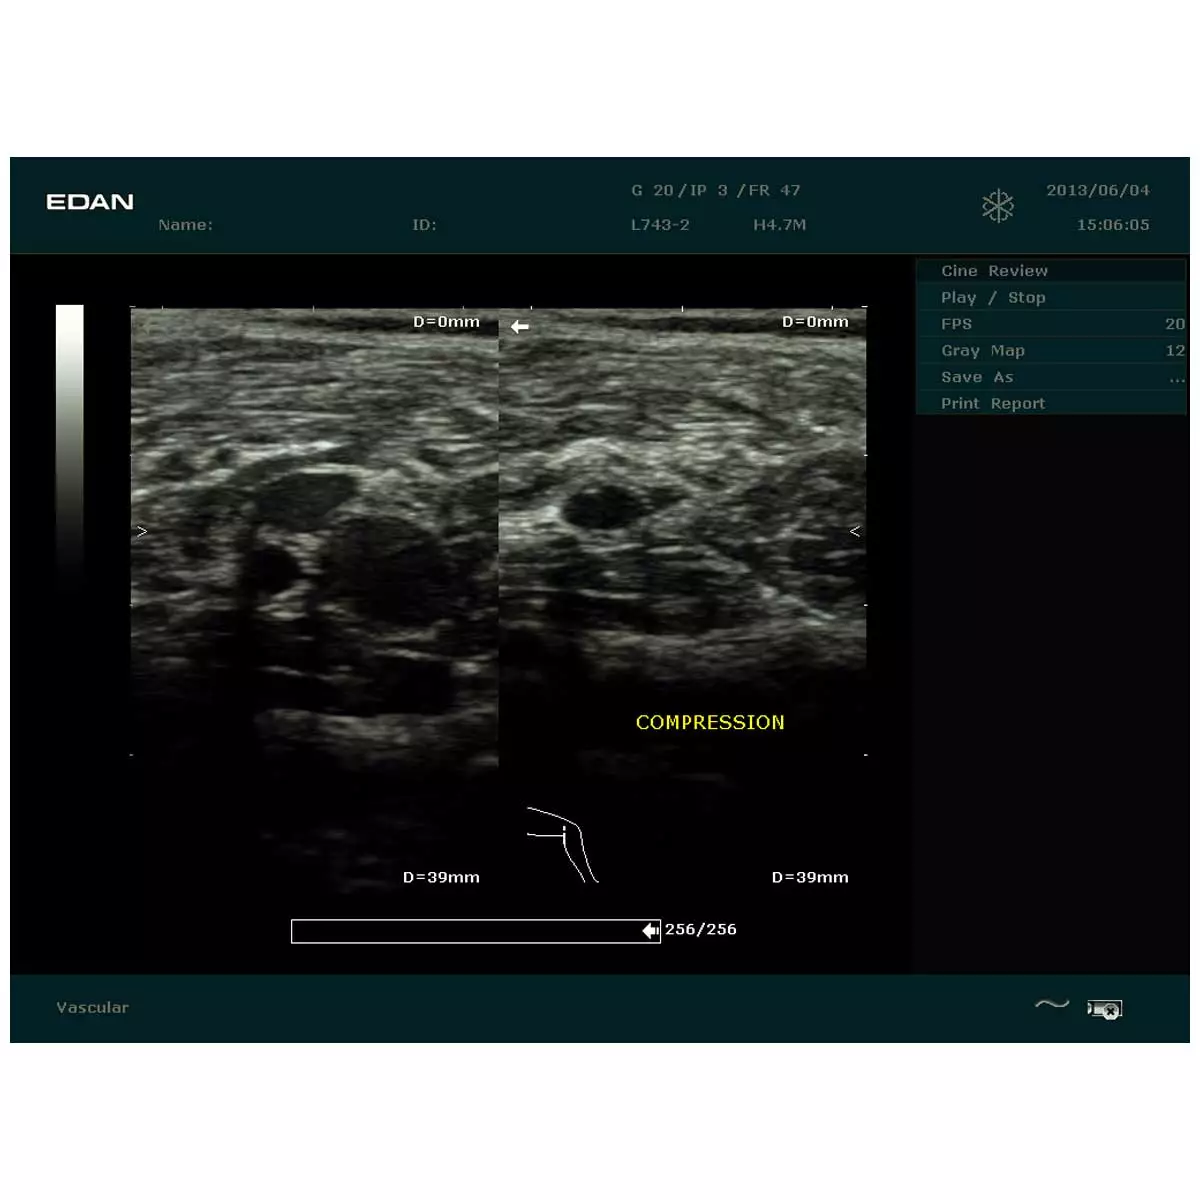

EDAN Échographe DUS 60

Échographe DUS 60 de EDAN

L'échographe DUS 60 de Edan convainc par une qualité d'image optimisée. En outre, le système d'échographie est facile à transporter et peut donc être utilisé à différents endroits. La technologie entièrement numérique de cet appareil permet de voir et d'évaluer les détails les plus infimes. Le clavier de l’échographe DUS 60 est équipé d'un rétroéclairage, ce qui rend l'échographie plus conviviale pour le patient, car l'appareil peut également être utilisé dans une salle d'examen sombre. Les résultats de la fonction Doppler et les images échographiques obtenues sont faciles à interpréter grâce à la fonction multi-pseudo-couleurs.

- Affichage en boucle des images : 256 images

- Moniteur 12,1" avec 256 niveaux de gris et fonction multi-pseudo-couleurs

| Modes d’affichage | mode B, mode M, doppler spectral, doppler PW |